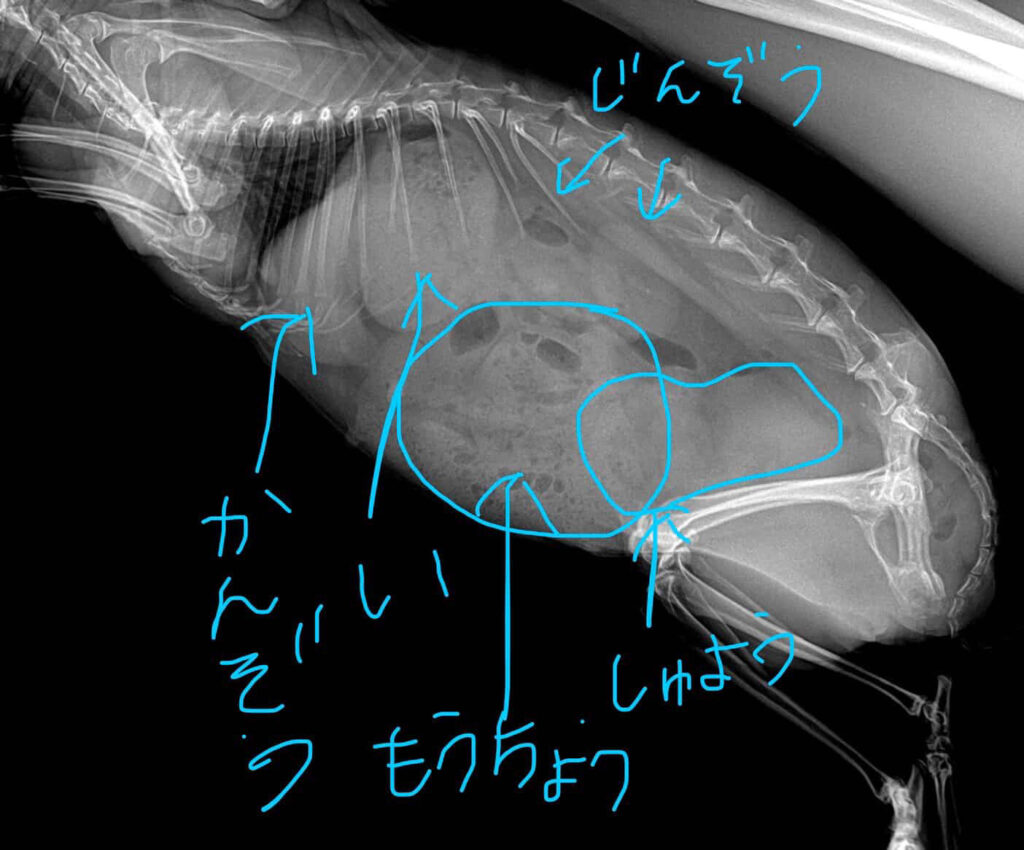

📷 【追記】ココさんの体が発していた「静かなSOS」〜画像診断が語る真実〜

記事を公開した後、ココさんのパパさんが「少しでも他の飼い主さんの参考になれば」と、当時のエコー写真とレントゲン写真の内容を詳しく教えてくださいました🍀

そこには、ココさんがどれほどの重荷を背負って頑張っていたのか、その証が記されていました😌

🔍 エコーで見えた「腫瘍」の正体

エコー検査(超音波検査)の画面に映し出されていたのは、やはり子宮の腫瘍でした。

パパさんが「テニスボールくらい」と言っていた通り、ココさんの小さなお腹を大きな腫瘍が圧迫し続けています😢